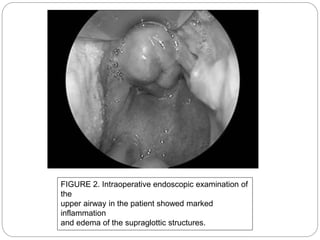

FIGURE 2. Intraoperative endoscopic examination of

the

upper airway in the patient showed marked

inflammation

and edema of the supraglottic structures.

FIGURE 2. Intraoperativeendoscopic examination of the upper airway in the patient showed marked inflammation and edema of the supraglottic structures.